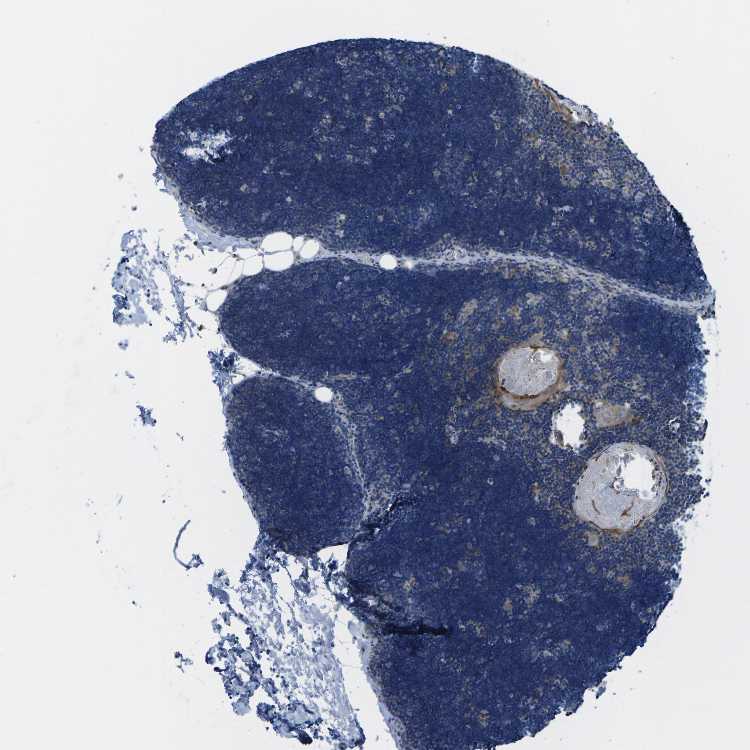

TISSUE PRIMARY DATA LYMPH NODE Show tissue menu

LYMPH NODE - Antibody stainingi

Antibody staining in the annotated cell types in the current human tissue is reported as not detected, low, medium, or high, based on conventional immunohistochemistry profiling in selected tissues. This score is based on the combination of the staining intensity and fraction of stained cells.

Each image is clickable and will lead to virtual microscopy that enables deeper exploration of all samples and also displays staining intensity scores, fraction scores and subcellular localization as well as patient and tissue information for each sample.

Antibody HPA015648

Germinal center cells Low

Non-germinal center cells Medium